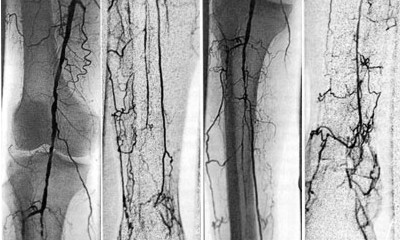

Arteriografía de Miembros Pélvicos Inferiores / Superiores.

El diagnóstico de la AOMI (Arteriopatía Obliterante de Miembros Inferiores) se basa en el examen clínico y en las imágenes vasculares, estas imágenes se obtienen a través de un estudio Arteriográfico de los miembros afectados, por medio del uso de Rayos X y medio de contraste.

La Arteriografía de Miembros, permite el estudio ya sea de los miembros superiores ó inferiores, pudiéndose detectar a través de ella, Coagulopatías, Isquemias Agudas por trombos, Estenosis, etc.

Arteriografia de Miembros Pelvicos Inferiores